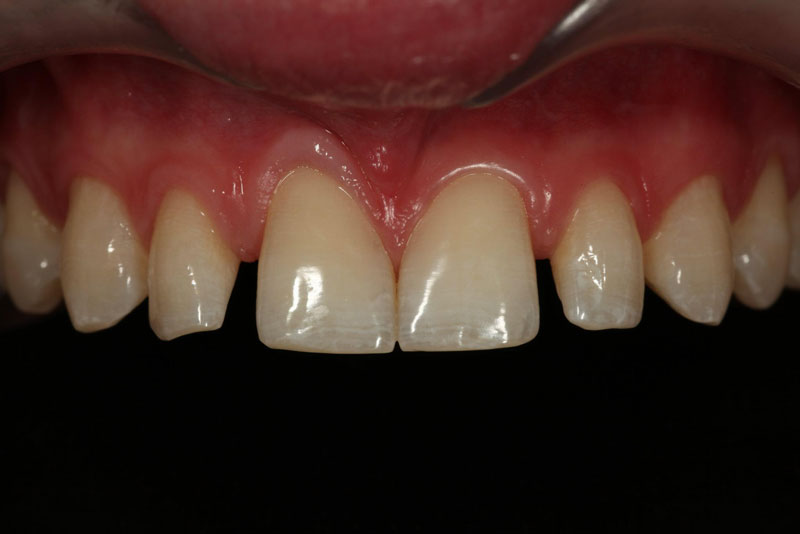

- Single Tooth: This is a microdontia localized to one tooth. Most peg laterals seen in a general dental practice setting will be of this type. See Fig. 3 (pre-op) and Fig. 4 (immediate post-op treated with direct resin).